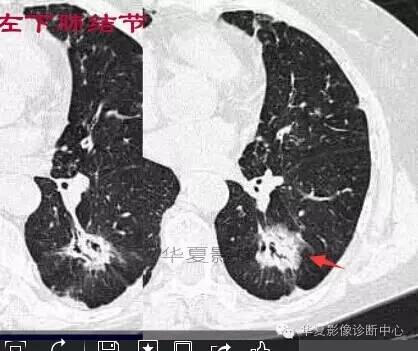

这一例是否GGO成分几乎没有

基本是实性的

那就按实性的分析

磨玻璃结节良恶性影像分析策略 都是支气管

胸膜凹陷,分叶征

宽基底与胸膜相连

近端有模糊的高密度影